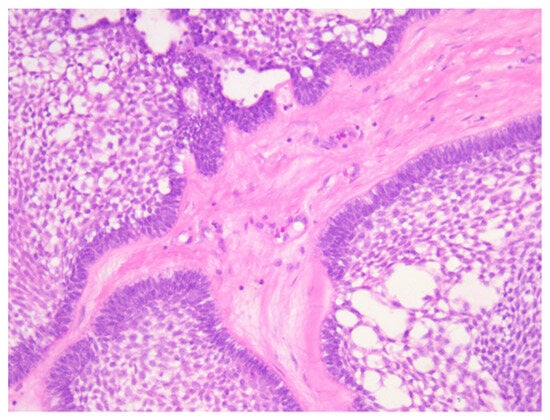

Histopathological examination showed tumor proliferation with a follicular, plexiform and solid (acanthomatous) pattern, with cyst formation. In a follicular pattern, islands of odontogenic epithelium were interspersed within a stoma of mature collagenous connective tissue. The islands had columnar cells at the periphery with reverse polarity and nuclei oriented away from the basal membrane, and the central portion of the islands presented loosely arranged epithelium cells that resemble the stellate reticulum of the developing enamel organ. The plexiform pattern showed an odontogenic epithelium arranged in long cords and stands that surrounded central areas of the supporting stroma. In addition to the interconnecting epithelium stands and cords, islands and sheets of tumors cells were observed. Also, the tumor showed areas of cystic degeneration, with the formation of micro- or macrocysts. Some islands of tumor cells demonstrated central areas of squamous differentiation, with the formation of keratotic pearls or individual keratinizations (Figure 4, Figure 5, Figure 6 and Figure 7). There were no signs of malignant transformation and no immunohistochemical reactions.

Figure 5. Histopathological aspects of ameloblastoma: (A,B) plexiform pattern, with anastomosing cords and trabeculae of odontogenic epithelial cells scattered in connective loose tissue with inflammatory cells; (C) acanthomatous pattern with squamous metaplasia and unicellular keratinization. HE staining, ob. 10×.